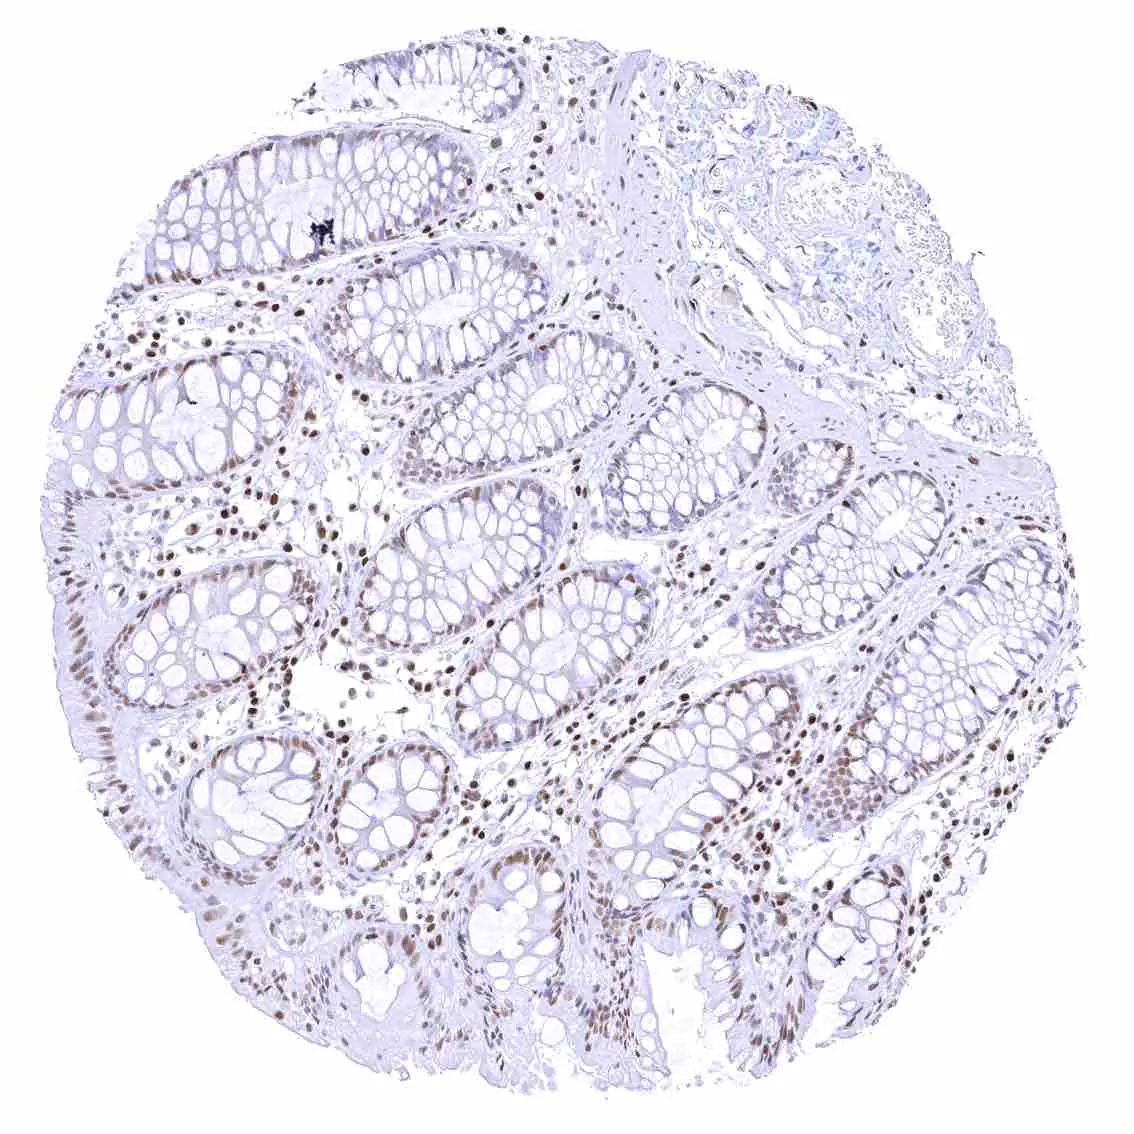

Appendix, mucosa – Among epithelial cells, nuclear p27 staining predominates in superficial epithelial cells. Most p27 staining occurs in lymphatic cells, however.